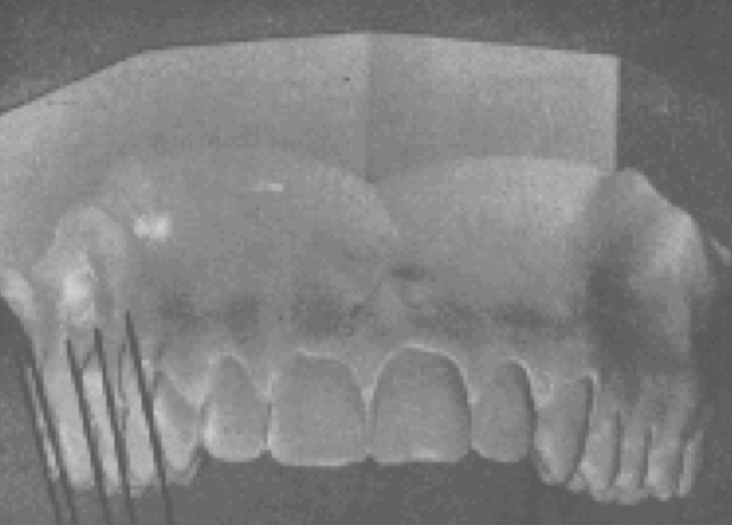

Molar relationship

Distal surface of the distobuccal cusp of the upper first permanent molar

occludes with the mesial surface of the mesiobuccal cusp of the lower second molar

Better opportunity for normal occlusion

The closer the distal surface of the distobuccal cusp of the upper first permanent molar approaches the mesial surfaces of the mesiobuccal cusp of the lower second molar